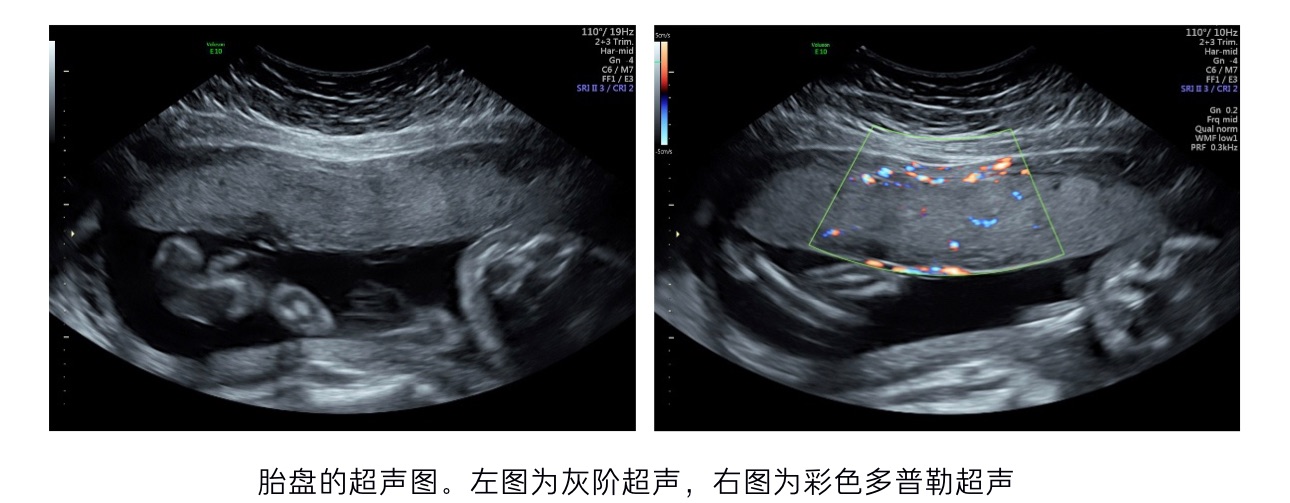

胎盘是联系宝宝与妈妈的一个重要桥梁,它具有营养输送、代谢物排出、免疫耐受等作用,对孕期母胎安全起到至关重要的作用。产前检查时,医生通常会给孕妇进行数次超声检查。这项检查能够快速地了解胎儿在宫内生长的情况。我们会发现,在超声报告中,除了有关于胎儿双顶径、头围、腹围等的描述之外,还会出现关于胎盘的描述。今天我们来认识一下胎盘这个重要但了解很少的人体器官。

在胎儿自身器官功能成熟前,胎盘扮演着肝脏、肺、小肠等脏器的角色。因此如果胎盘功能损伤会带来灾难性的后果,比如流产、早产、死产、胎儿生长受限、先兆子痫等等。其中先兆子痫不仅仅会威胁到胎儿,甚至会威胁到母亲的生命安全。大多数的先兆子痫孕妇的胎盘体积明显偏小,病理学检查中也会出现更多、更严重的异常表现。越来越多的研究表明,胎盘功能异常会改变母婴健康状况,而这一改变可能是永久性的。在产前,我们往往难以确切的获知胎盘功能的改变,但超声技术给我们了解胎盘提供了帮助。

在产前超声中除了会关注胎儿本身之外,还通常会对胎盘进行检查,检查内容一般为附着部位、厚度、胎盘位置等。这些检查内容分别代表什么呢?除了这些以外,超声还可以怎么评估胎盘呢?

在常规的产前超声中,我们一般会首先观察胎盘附着部位以及胎盘位置。胎盘附着部位一般会被描述为前壁、后壁、宫底部等,这里的前壁、后壁是指的子宫壁。胚胎进入子宫腔内后,它会寻找合适的位置完成植入(着床)的过程,植入点可能是子宫蜕膜(妊娠期子宫内膜)的任意部位,因此会形成前壁胎盘、后壁胎盘等。不同的胎盘附着部位正常情况下并不会对胎儿造成影响。

胎盘附着位置、厚度、分级等均是针对胎盘形态学进行检查,然而这些并不足以反应胎盘功能。随着技术的不断发展,学者们开始采用更多新的超声技术,在保障母胎安全的前提下,努力地探索胎盘功能的精准评估。